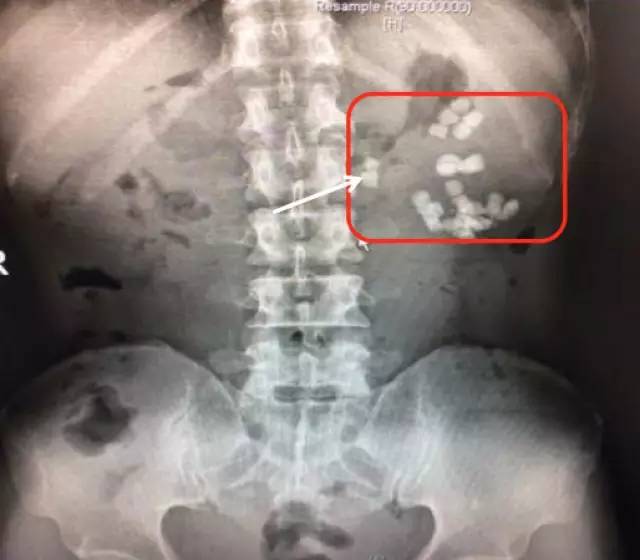

入院后进一步行泌尿系CT平扫+三维重建

(白色箭头提示的就是多发的残留结石)

泌尿系CT:红箭头示左肾重度积水;白箭头示多发结石

白色箭头所指就是引起梗阻的掉到输尿管的结石

CT三维重建图像可见左肾明显增大、扩张积水、多发结石